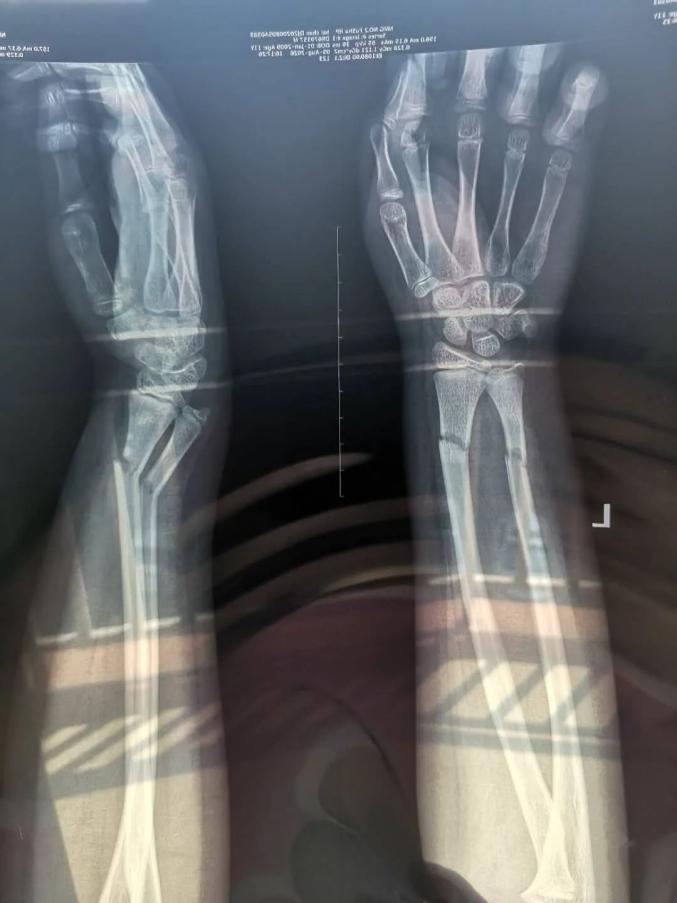

医院一检查诊断出

孩子的双臂骨折